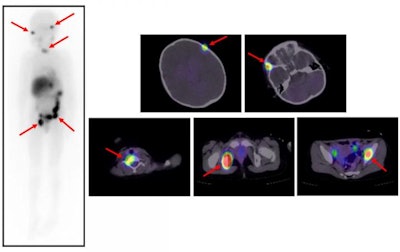

Scintigrams at 131I-MIBG therapy. Multiple 131I-MIBG accumulations are seen in bone metastases (red arrows). β rays emitted from 131I-MIBG attack tumor cells in the bone metastases. Image courtesy of Kanazawa University.The researchers found the following:

- The event-free survival rate (the time after treatment that the patient was free of complications) was 42% at one year and 16% at five years.

- The overall survival rate was 58% at one year and 42% at five years.